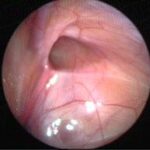

Can this operation be done laparoscopically?

Operation in hydrocele involves closing of the open passage through which the testis has come down. This can be done from outside as in open surgery or from inside by laparoscopy. With the help of laparoscopy we are able to look at the opposite side to see if the passage is open on that side as well. This can be closed at the same sitting if you wish to. Recovery from surgery, timing of surgery and discharge from hospital are the similar for open surgery and laparoscopic surgery.